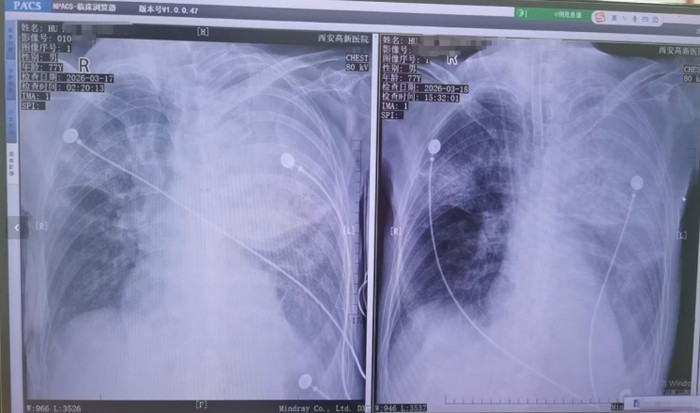

胡先生说,起初以为是伤风,入院诊治莫得成果,还越来越严重,以至于病情危重,“整个这个词肺部全白了”,况兼出现呼吸繁重,病院以至下了病危文牍书。3月17日,家东谈主赶快将父亲转院到西安高新病院抢救,到病院以后就住进了ICU。经查验,才发现是鹦鹉热衣原体感染导致的重症肺炎。胡先生提供的一份《西安高新病院会诊证明》显现,胡先生的父亲3月17日以重度肺炎入院。会诊为重症肺炎(鹦鹉热衣原体感染)I型呼吸繁重、急性呼吸困窘轮廓征、脓毒症等。